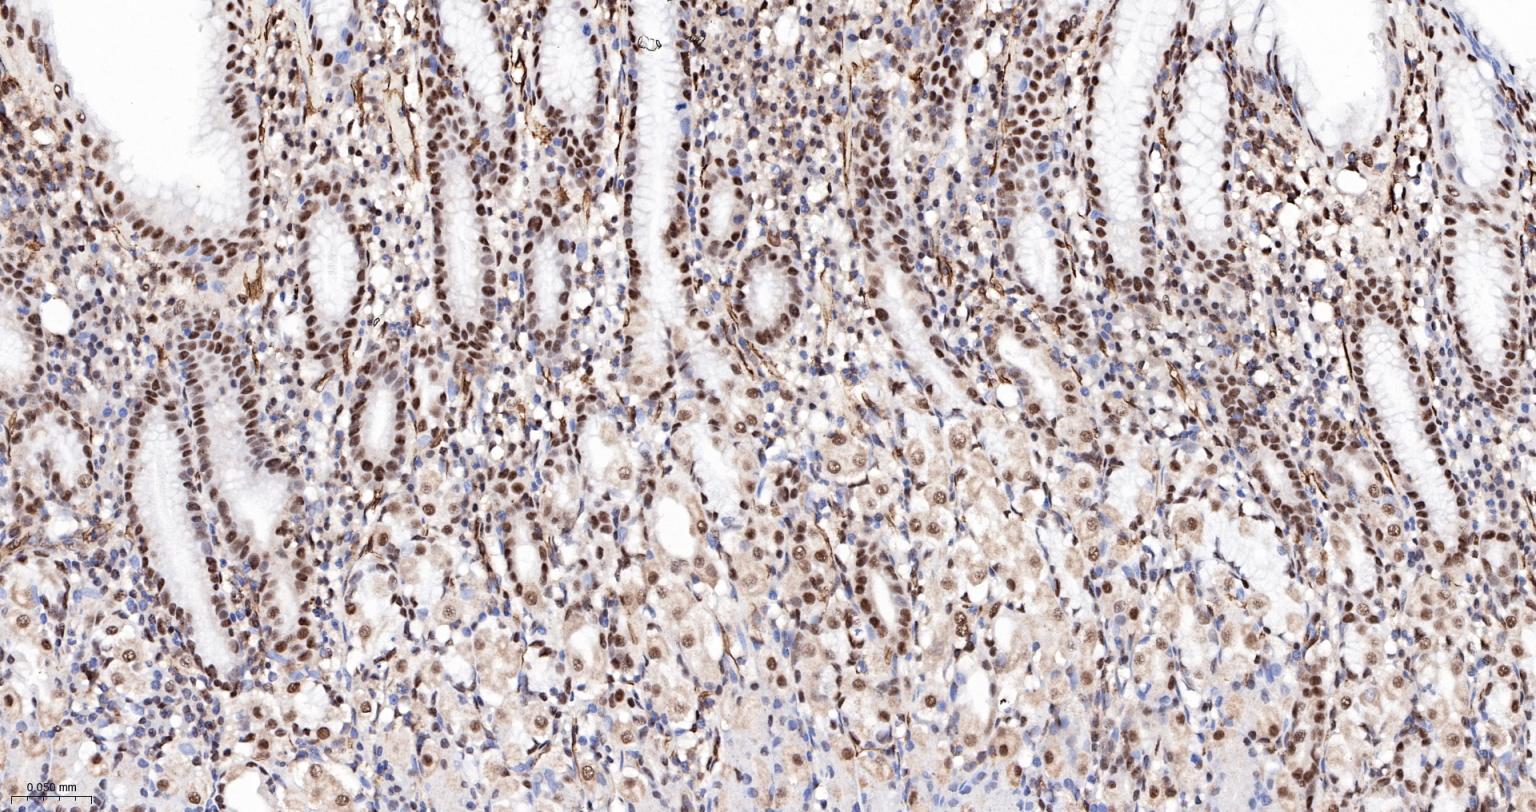

Paraformaldehyde-fixed, paraffin embedded Human Breast Cancer; Antigen retrieval by boiling in sodium citrate buffer (pH6.0) for 15 min; The section was incubated with PRPF19 Monoclonal Antibody, Unconjugated (bsm-61268R) at 1:200 overnight at 4°C, followed by conjugation to the bs-0295G-HRP and DAB (C-0010) staining.